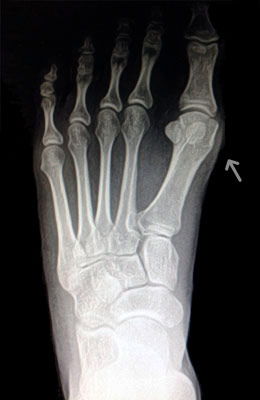

Minimally Invasive Bunion Surgery featuring the CrossRoads miniBunion™ System

Eva is a 24-year-old female who had just began working at a job that required high fashion shoes. She was in constant pain but could not take time off work. Our miniBunion™ Minimally Invasive Bunionectomy allowed her to continue to work and be on her foot with full recovery and return to regular shoes by 6 weeks. She had an amazing range of motion, no more bunion pain, and absolutely no visible incision. After picture taken six weeks post-surgery.